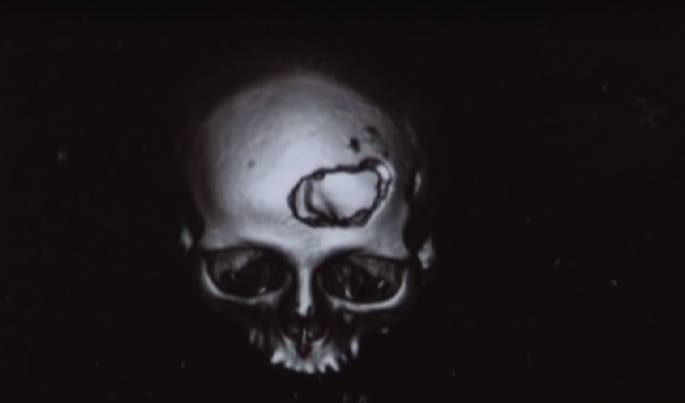

А вот жертвам побоища пришлось провести долгое время в больнице. Они стали инвалидами и потеряли работу. Жена нападавшего в следствие открытого пролома черепа Татьяна похудела на 20 килограммов, сейчас у нее начались проблемы со зрением, слухом и памятью. А у дочери Юлии были две открытые черепно-мозговые травмы и осколочный перелом свода черепа. Теперь у нее бессонница и головокружения. С такими открытыми ранами в голове ей нельзя даже выходить на улицу.

Татьяне и Юлии крайне необходимо поставить титановые пластины. Стоимость операций — порядка 3 тысяч долларов. В семье таких денег нет. Если у вас есть возможность помочь, средства можно перевести на карточку ПриватБанка 4149 4978 4961 4146, Юлия Игоревна Рыбак.